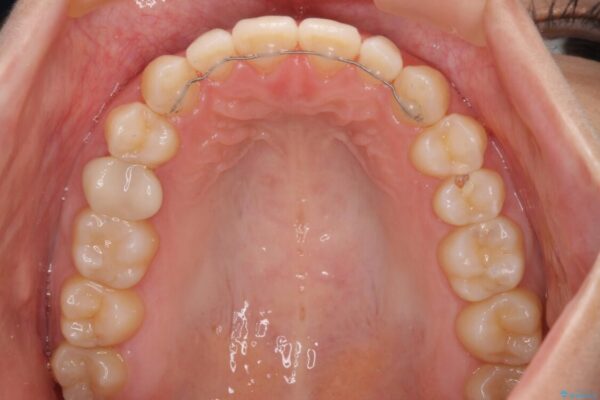

治療途中

• 隙間だらけの歯列 インビザラインで改善 治療途中画像